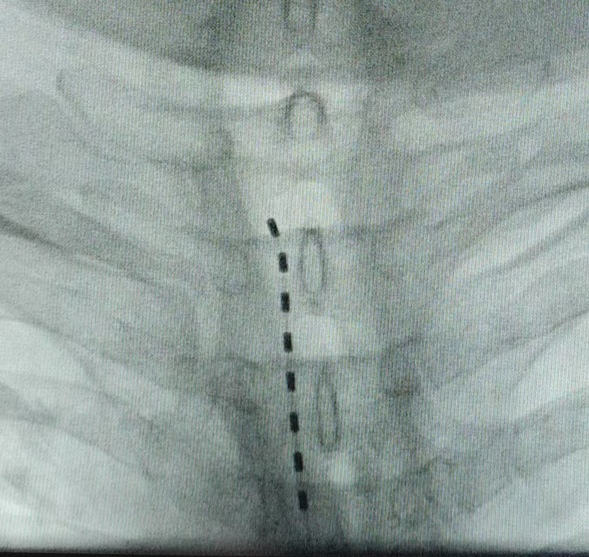

电极植入

术中操作

脊髓电刺激植入术是通过穿刺的方法,在脊髓附近放个“小电极”,发出微弱的电流,像干扰信号一样,把疼痛信号挡在大脑外,让你感觉不到疼。目前,这是治疗带状疱疹后遗神经效果最好的治疗方法,对于经针灸、拔罐、封闭针、截根等方法仍无法缓解疼痛的患者,依然有着很好的治疗效果,具有无痛、损伤小、镇痛效果确切等优点。在止疼的同时,可对受损的神经进行恢复,有效改善疼痛,同时缓解神经受损产生的皮肤麻木、瘙痒等症状。